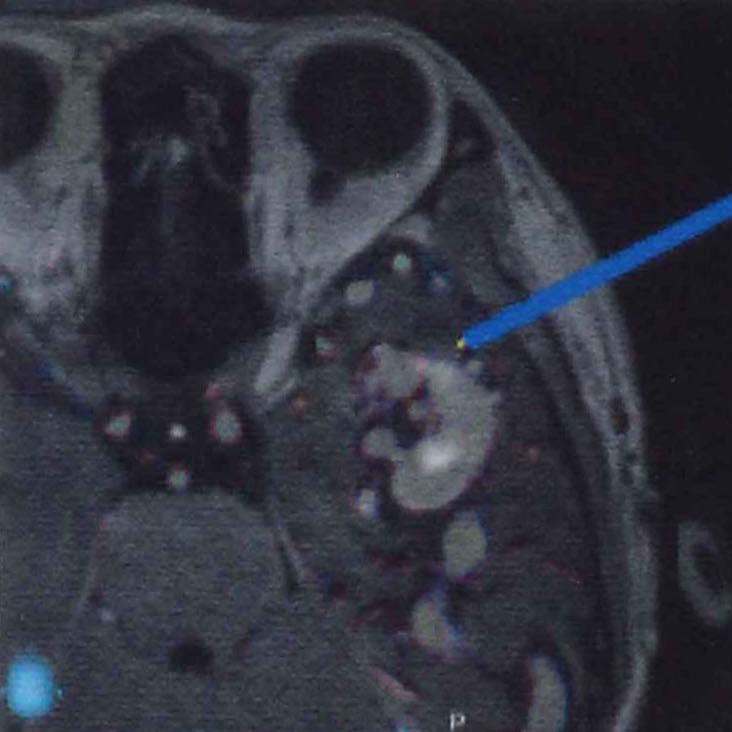

脳血管撮影

手術前

手術後

手術中